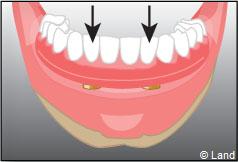

Exemple de 3 dents manquantes remplacées par 3 couronnes sur implants.

Pose des piliers prothétiques et des 3 couronnes scellées.